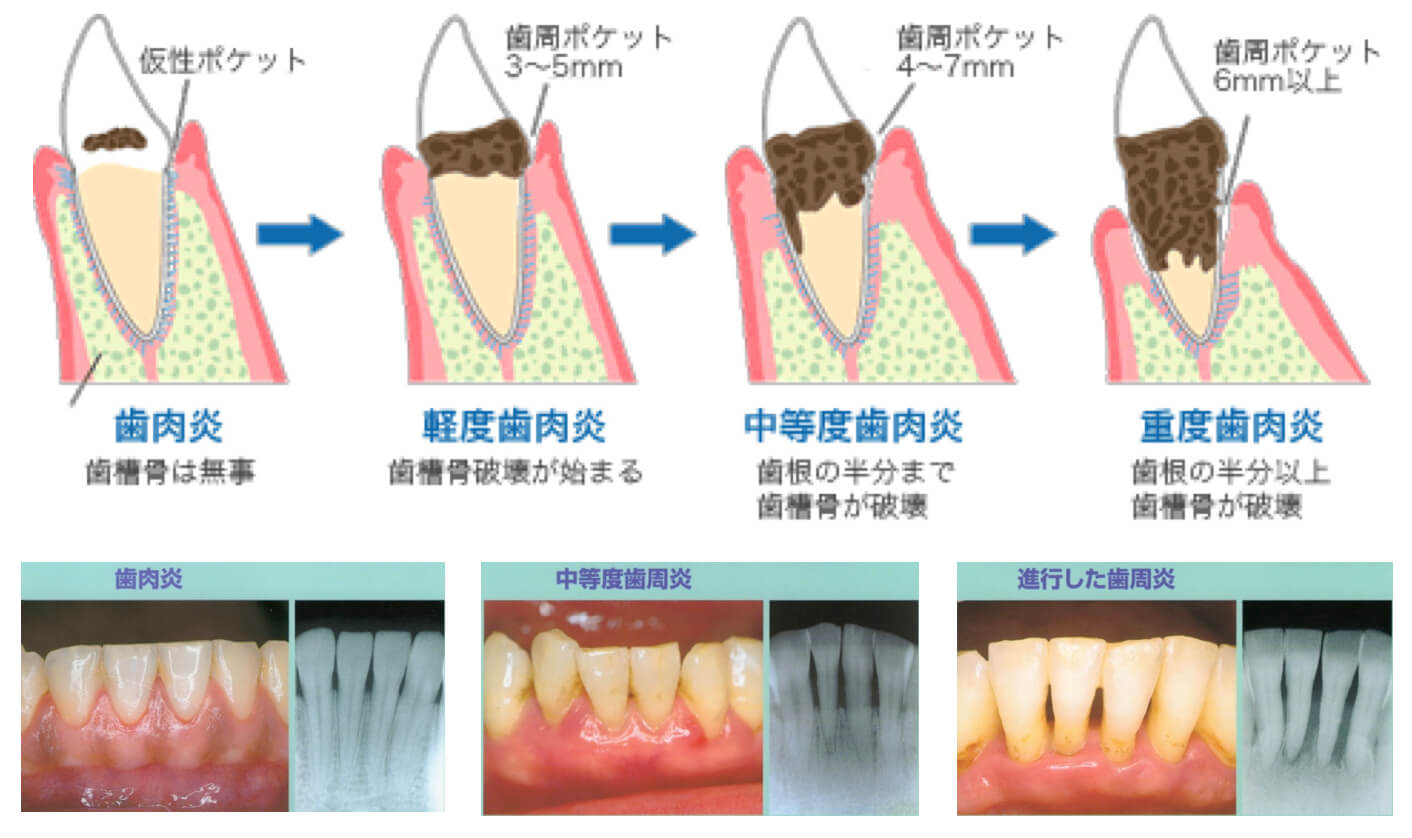

歯周病は骨が下がる病気

歯周病は、痛みがないまま進行します。

そのため、30代以降の方の80%が、歯周病になっています。